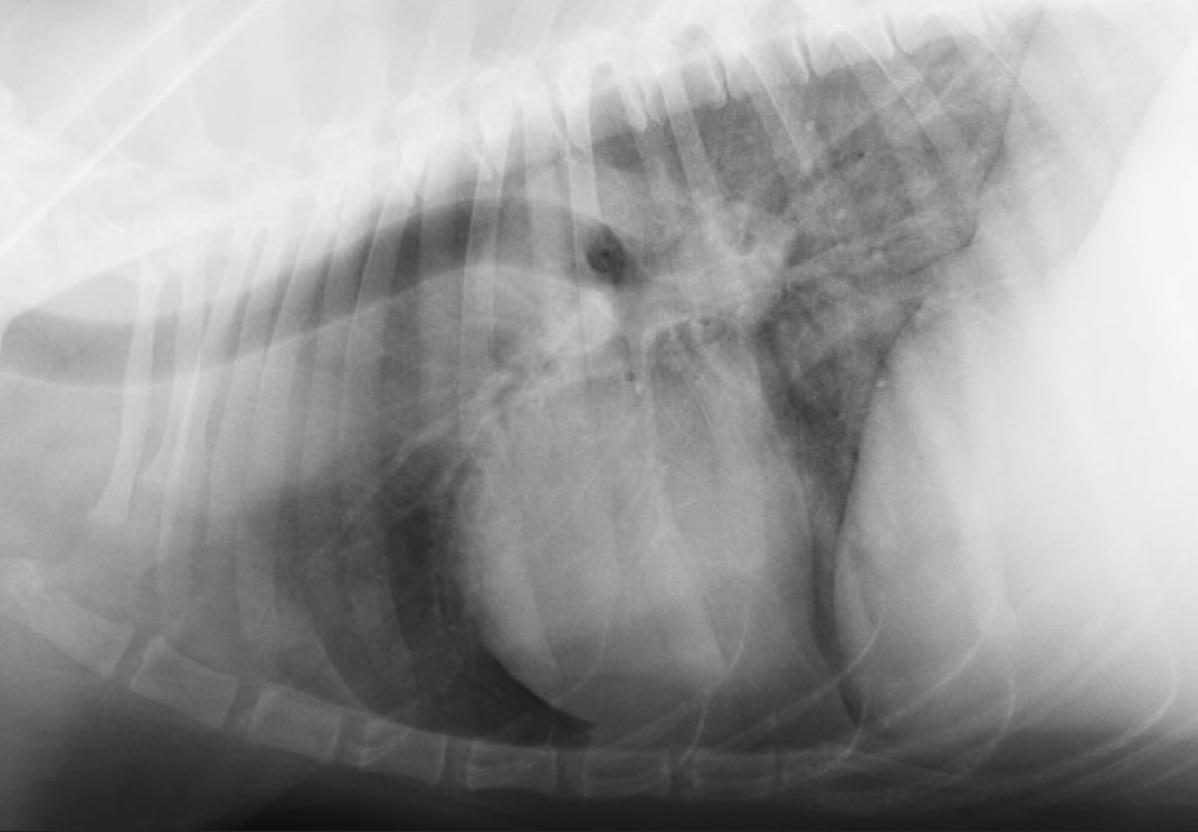

23

Q

A

mediastinal lymph node enlargement

ventral to trachea

+/- dorsal tracheal displacement

wide/convex cranial mediastinum (not straight line)